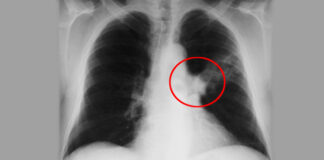

5 shenja që paralajmërojnë se nuk keni oksigjen të mjaftueshëm në...

Frymëmarrja është një veprim i pavullnetshëm që trupi ynë bën, pavarësisht nëse me vetëdije i kushtojmë vëmendje apo jo. Kjo do të thotë që...